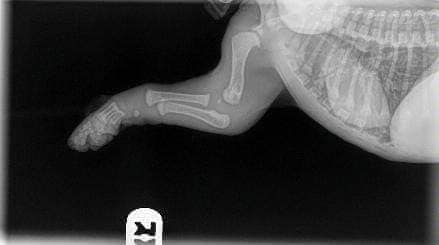

Un peu d'histoire: il s'agit d'un bébé chiot (nouveau-né) qui a eu un coup au coude et ne l'a pas utilisé correctement, il a donc été emmené chez le vétérinaire. Il n'y a rien de mal dans ces radiographies, heureusement, c'était une blessure aux tissus mous et il devrait être en bonne santé.